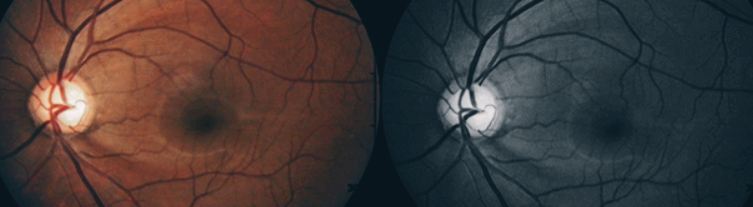

안압과 시신경 혈류의 저하로 시신경이 시간이 지날수록 파괴되어 시야가 좁아지게 되는 안과질환입니다. 보통 40대 이후에 점차적으로 안 좋아질 가능성이 높지만 요즘은 다양한 외부요인으로 인해서 20,30대 젊은 세대들에게도 발생하는 질환입니다.

녹내장은 실명 원인으로 2번째에서 3번째로 높으며, 녹내장은 이미 벌써 진행된 상태에서 발견이 된다면 회복이 거의 불가능하기 때문에 녹내장 초기증상이 나타난다면 바로 병원을 찾아서 치료를 시작하시는 것이 시력과 시야를 최대한 유지하는데 도움이 됩니다.

녹내장 원인은 시신경 기능에 문제가 발생해서 시력 상실로 이어지는 질환인데요. 시신경은 우리가 눈을 통해서 앞을 보게 해주는 중요한 부분인데, 이곳에 문제가 생겨나는 정확한 원인으로 밝혀진 것은 아직은 없습니다.

하지만 녹내장 원인으로 의심할 수 있는 요소들은 안압이 올라감으로써 증상이 생기는 경우인데요. 간혹 안압이 정상임에도 불구하고 문제가 생기는 경우도 있다고는 하는데, 이는 유전적인 요인과 환경적 요인 즉, 고혈압과 당뇨, 심혈관 질병, 근시 등이 녹내장 원인이 되기도 합니다.